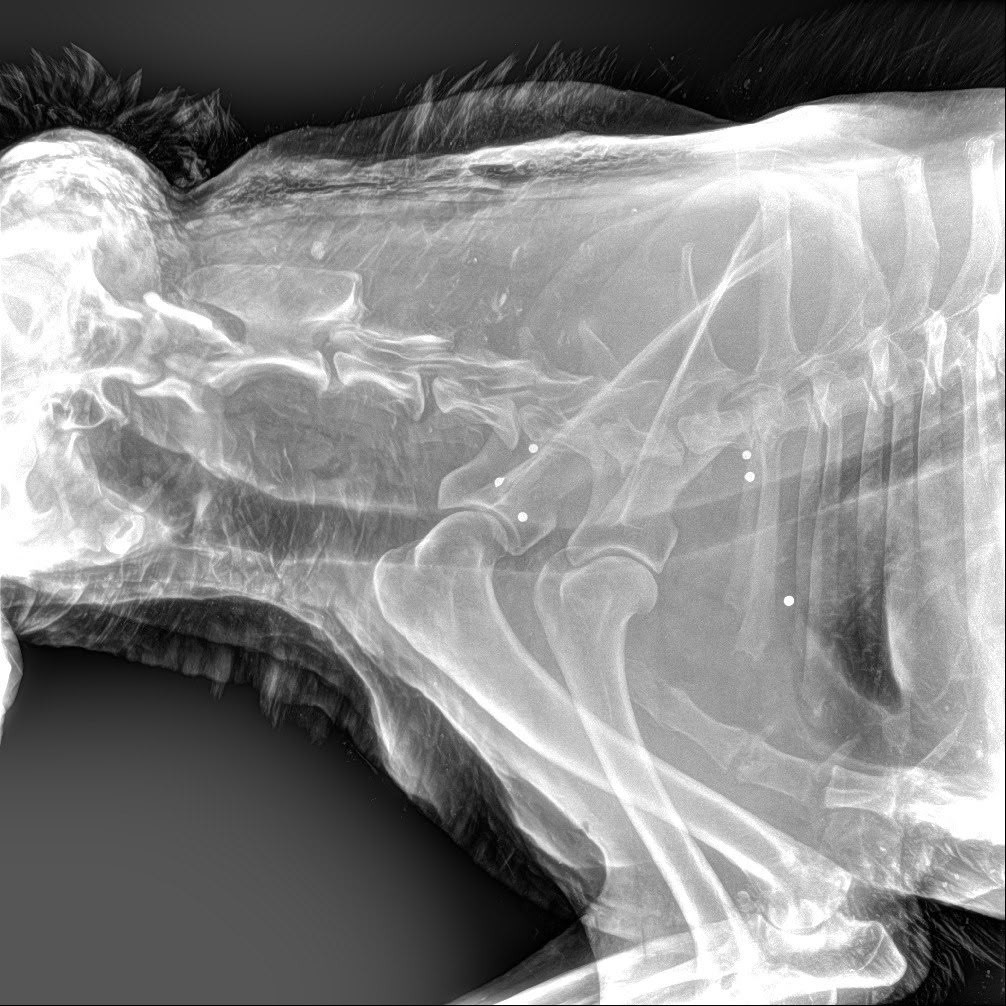

Специалисты доставили собаку в ветеринарную клинику, где рентген показал многочисленные огнестрельные ранения. В теле животного обнаружили пули разной степени давности, передает телеграм-канал Mash на Мойке.